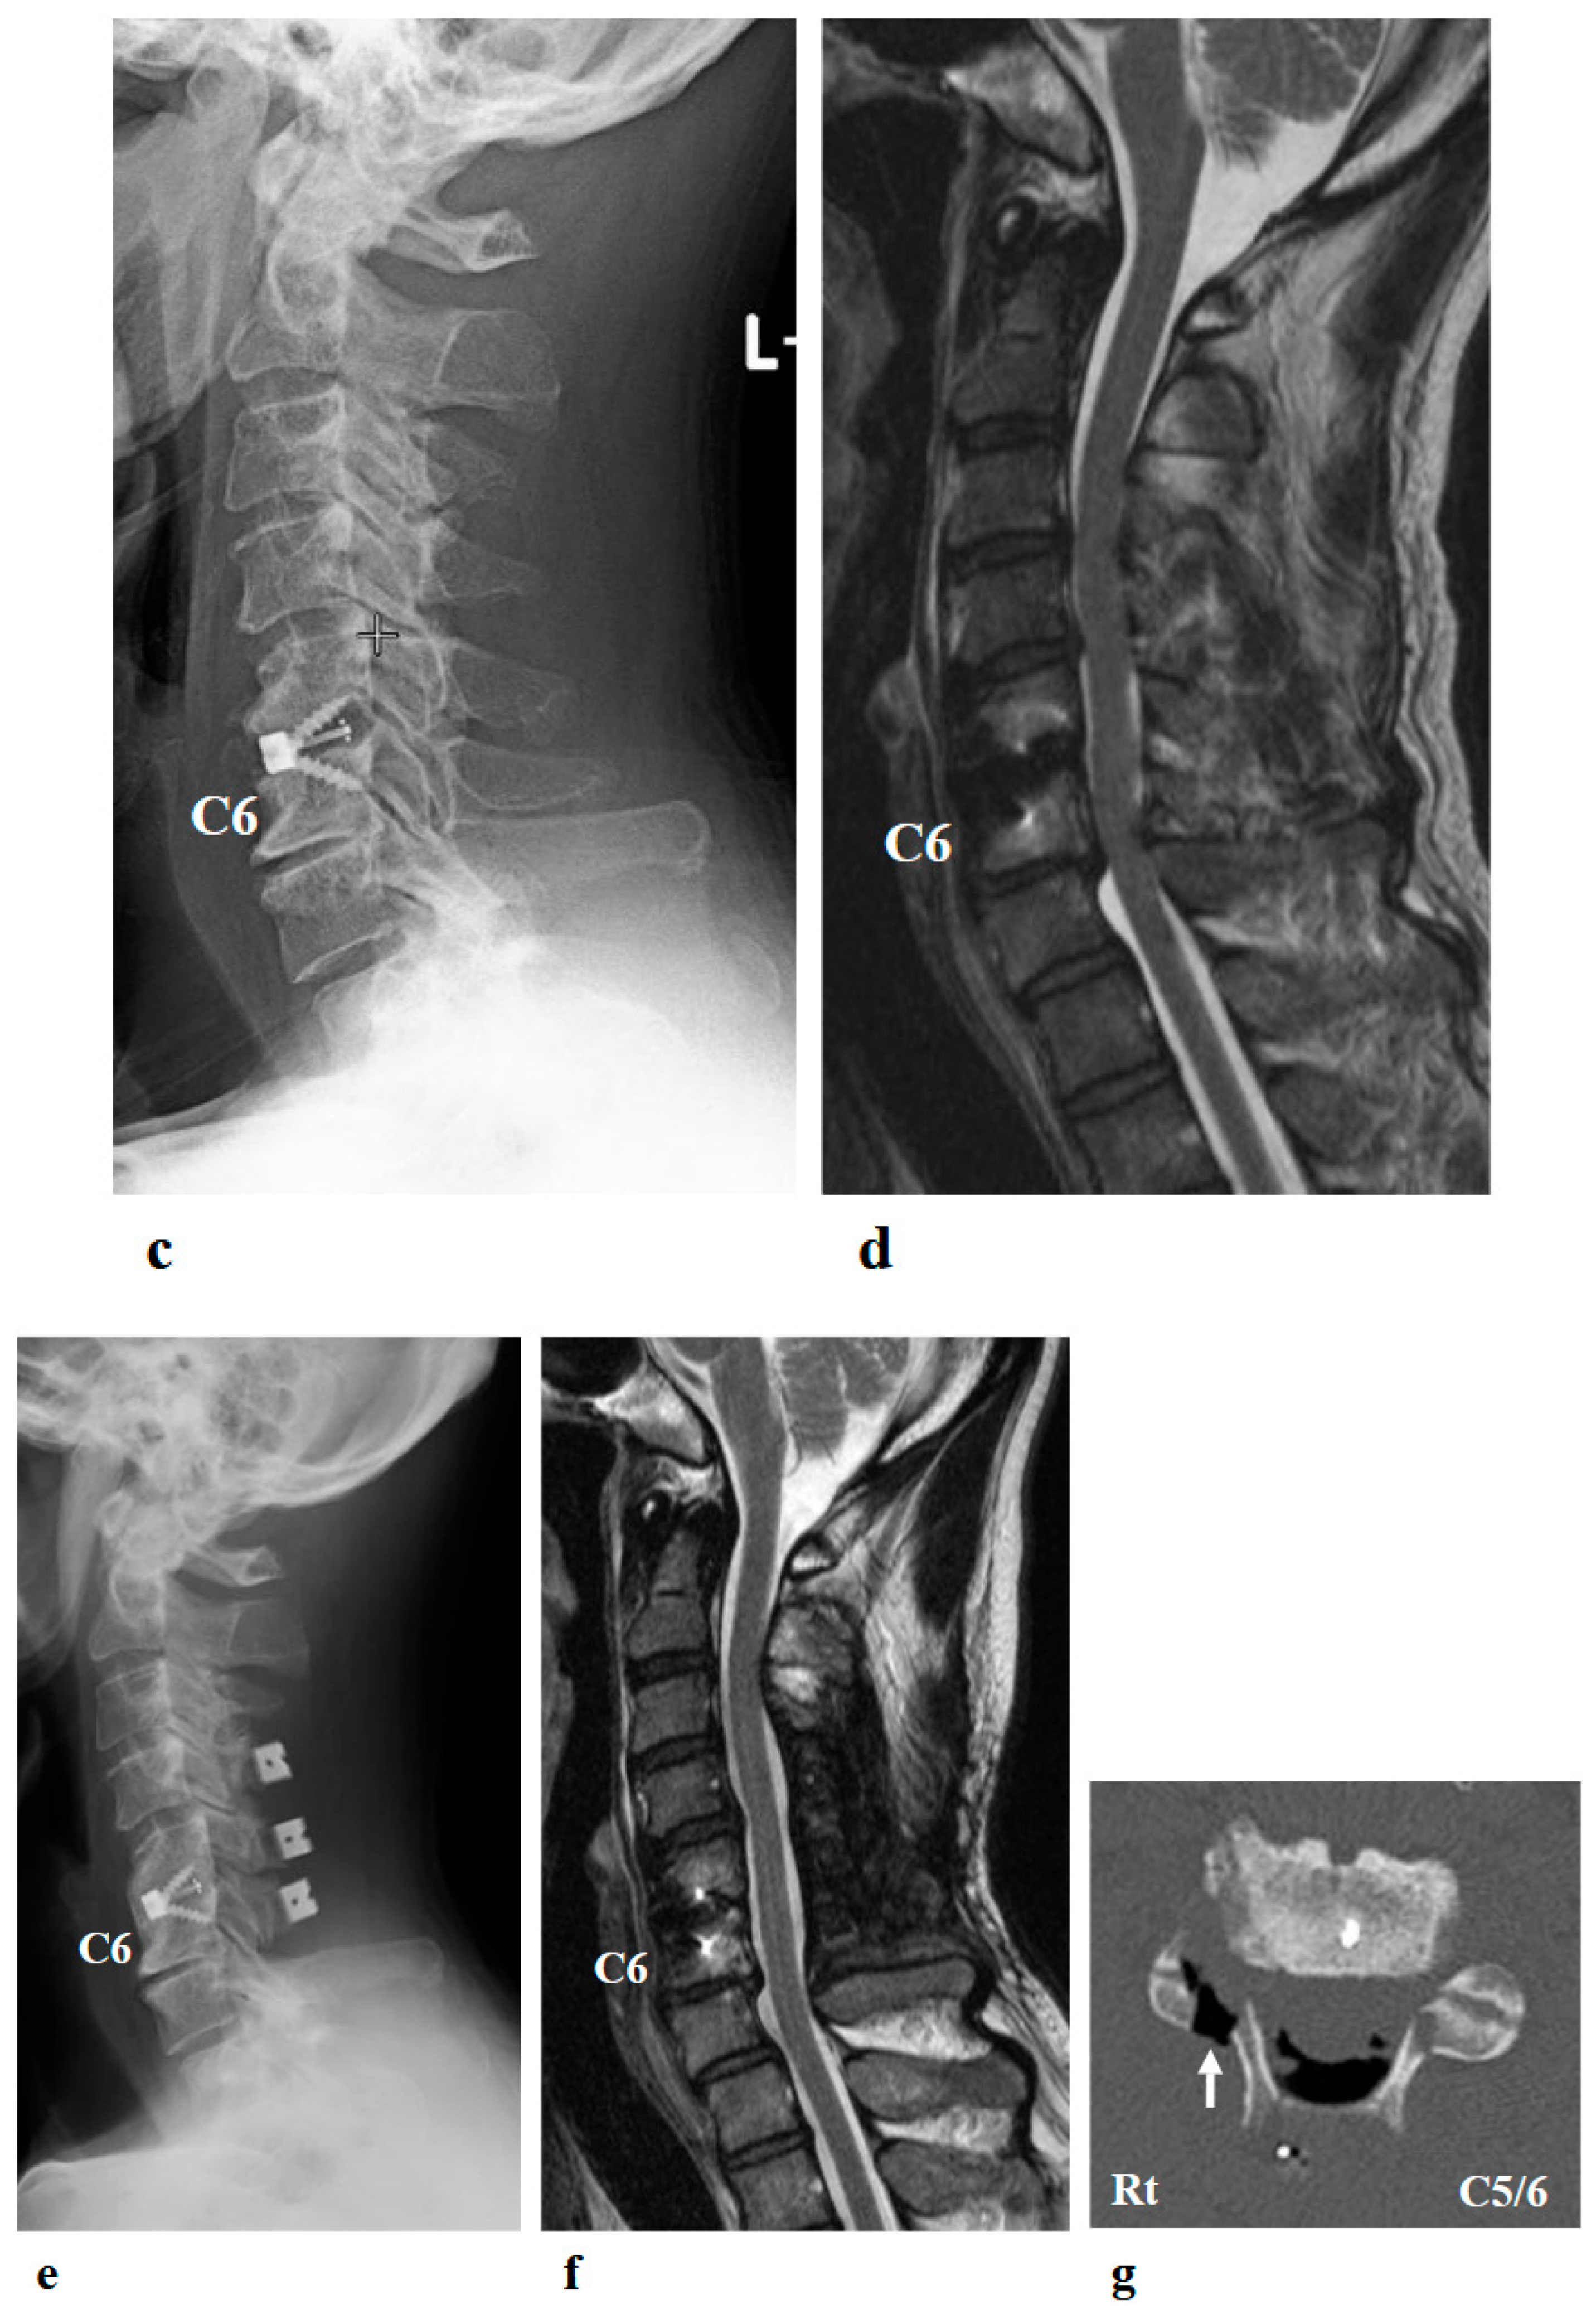

Figure 2.

Preoperative (a,b) and postoperative (c,d) images following the first surgery, as well as postoperative images from the second surgery (e–g). (a) Lateral cervical spine X-ray showing narrowing of the intervertebral disc space and osteophyte formation at C5–C6 and C6–C7. (b) Reconstructed mid-sagittal CT image after myelography revealing spinal cord compression at C5–C6 and C6–C7, and posterior displacement of the C5 vertebral body. (c) Postoperative lateral cervical spine X-ray after anterior decompression and fusion at C5–C6. (d) Mid-sagittal cervical MRI demonstrating persistent spinal cord compression from C3–C4 to C6–C7. (e) Postoperative lateral cervical spine X-ray after C4–C6 laminoplasty and partial laminectomy at the caudal aspect of C3 and the cranial aspect of C7. (f) Mid-sagittal cervical MRI showing adequate spinal cord decompression from C3–C4 to C6–C7. (g) Axial CT image at the C5–C6 level showing adequate right C5–C6 foraminotomy (arrow).

A 46-year-old man presented to the outpatient clinic of our hospital with a chief complaint of right-sided C5 palsy that had persisted for 41 months following cervical spine surgery (Figure 1). At the age of 43, he noticed a decrease in grip strength in his right hand and numbness in his right upper limb, and visited another hospital. Examinations at that hospital revealed that his initial symptoms were caused by cervical spondylotic myelopathy due to spinal cord compression from degenerative cervical vertebrae (Figure 2a,b). Based on the diagnosis, at that hospital, he underwent anterior decompression and fusion surgery at the C5–C6 level (Figure 2c). Prior to initiation of HAL therapy at our hospital, his neurological assessment was as follows: Numerical Rating Scale for pain = 4, American Spinal Injury Association (ASIA) motor score = 97, and ASIA sensory score = 108.

Postoperative imaging revealed spinal cord compression extending from C3–C4 to C6–C7 (Figure 2d). Based on the imaging findings, inadequate spinal cord decompression from the initial surgery was diagnosed, and he underwent an additional cervical spine surgery at the same hospital 20 months later. The second surgery consisted of C4–C6 laminoplasty and partial laminectomy at the caudal aspect of C3 and the cranial aspect of C7 (Figure 2e). During the procedure, surgical intervention for post-operative C5 palsy was concurrently undertaken, specifically a right C5–C6 foraminotomy.

Two days after the second surgery, he experienced pain extending from his neck to his right shoulder, followed by difficulty in elevating his right upper limb. Postoperative MRI demonstrated adequate spinal cord decompression with no obvious abnormal findings (Figure 2f). Post-operative CT confirmed the right C5–C6 foraminotomy was appropriately performed (Figure 2g, arrow).